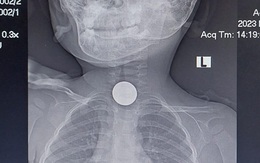

Lấy dị vật là đồng xu trong thực quản bé trai 31 tháng tuổi

Các bác sĩ ở Phú Yên đã nội soi lấy dị vật là một đồng xu kẹt trong thực quản bé trai 31 tháng tuổi quê tỉnh Gia Lai.